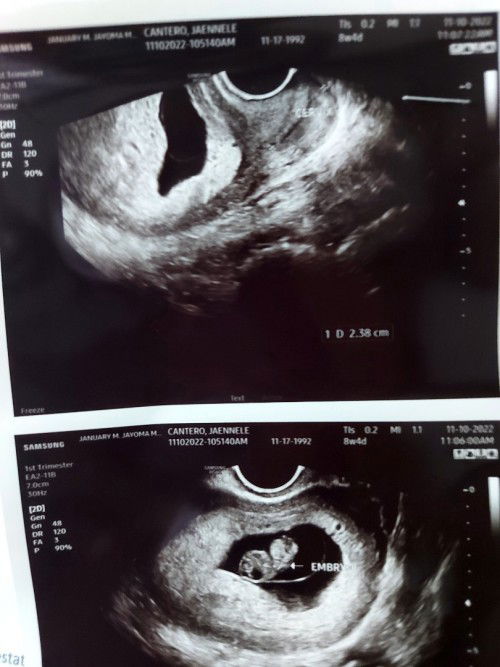

2 months pregnant po ako. And sabi nang ob gynecologist ko sakin short cervix po ako nasa 2.38 cm ๐

Better pa 2nd opinion ka sis, baka need mopo magpa cerclage. Ako 2.1 lang cervix length ko at 13 weeks inischedule nako ng ob ko ng cerclage para maprevent pre term labor

trans vaginal yung ginawa sis